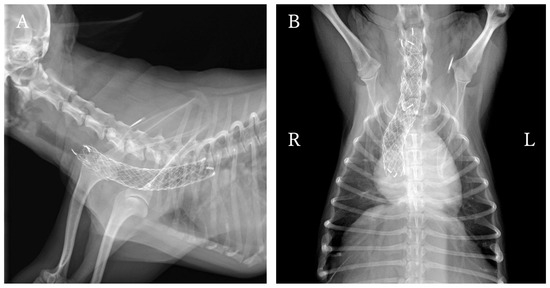

Tracheal stent fracture is a major complication of endoluminal tracheal stent (ELS) for canine tracheal collapse, and optimal management strategies remain unclear. A 4-year-old Yorkshire Terrier presented with respiratory distress caused by complete ELS fracture. Imaging and bronchoscopy revealed intraluminal protrusion of fractured stent segments, ventral tracheal cartilage invagination, and marked luminal deformation. A polypropylene linear prosthesis (PLLP) was selected as an external tracheal support. Its continuous band-like structure allowed broad and uniform reinforcement of the tracheal wall and redistribution of mechanical stress. PLLP placement successfully restored a near-normal tracheal contour and stabilized the fractured stent without introducing additional intraluminal material. Postoperative bronchoscopy confirmed improved tracheal patency, and no further deformation or stent damage was observed despite several months of altered airway dynamics associated with laryngeal paralysis. This case suggests that PLLP may represent a valid surgical option for managing tracheal stent fracture in dogs. Full article